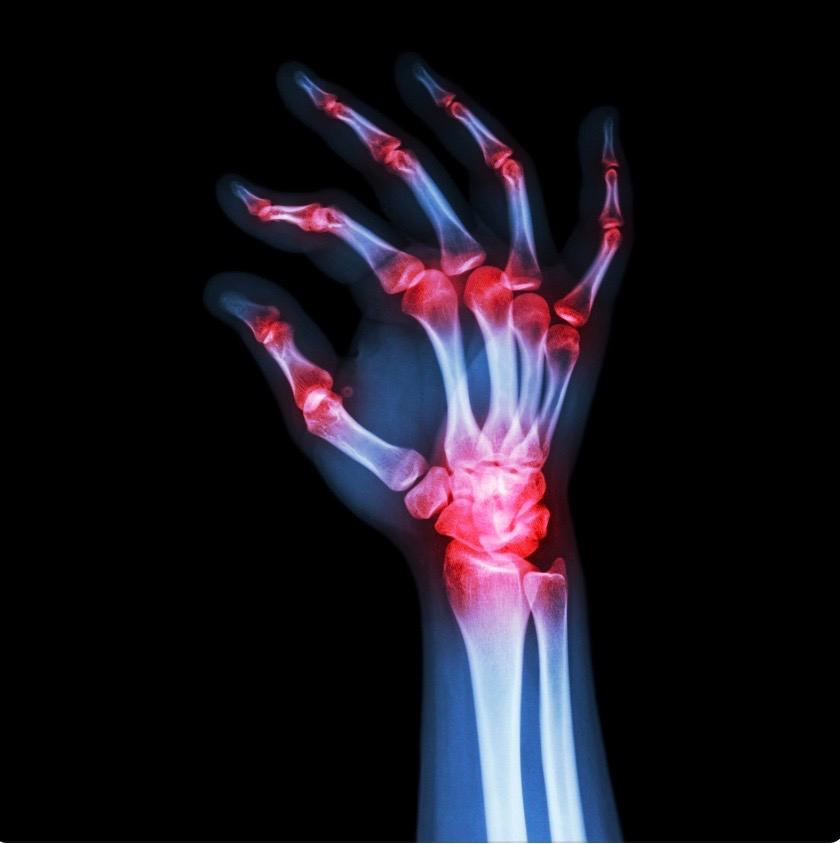

Imaging Studies

- X-rays: X-rays of the affected joints can reveal characteristic changes associated with RA, such as joint erosion, joint space narrowing, and bone damage

- Ultrasound: Ultrasound imaging can detect synovial inflammation, joint effusion, and soft tissue abnormalities

- Magnetic Resonance Imaging (MRI): MRI scans provide more detailed images of joint inflammation, cartilage damage, and bone erosion